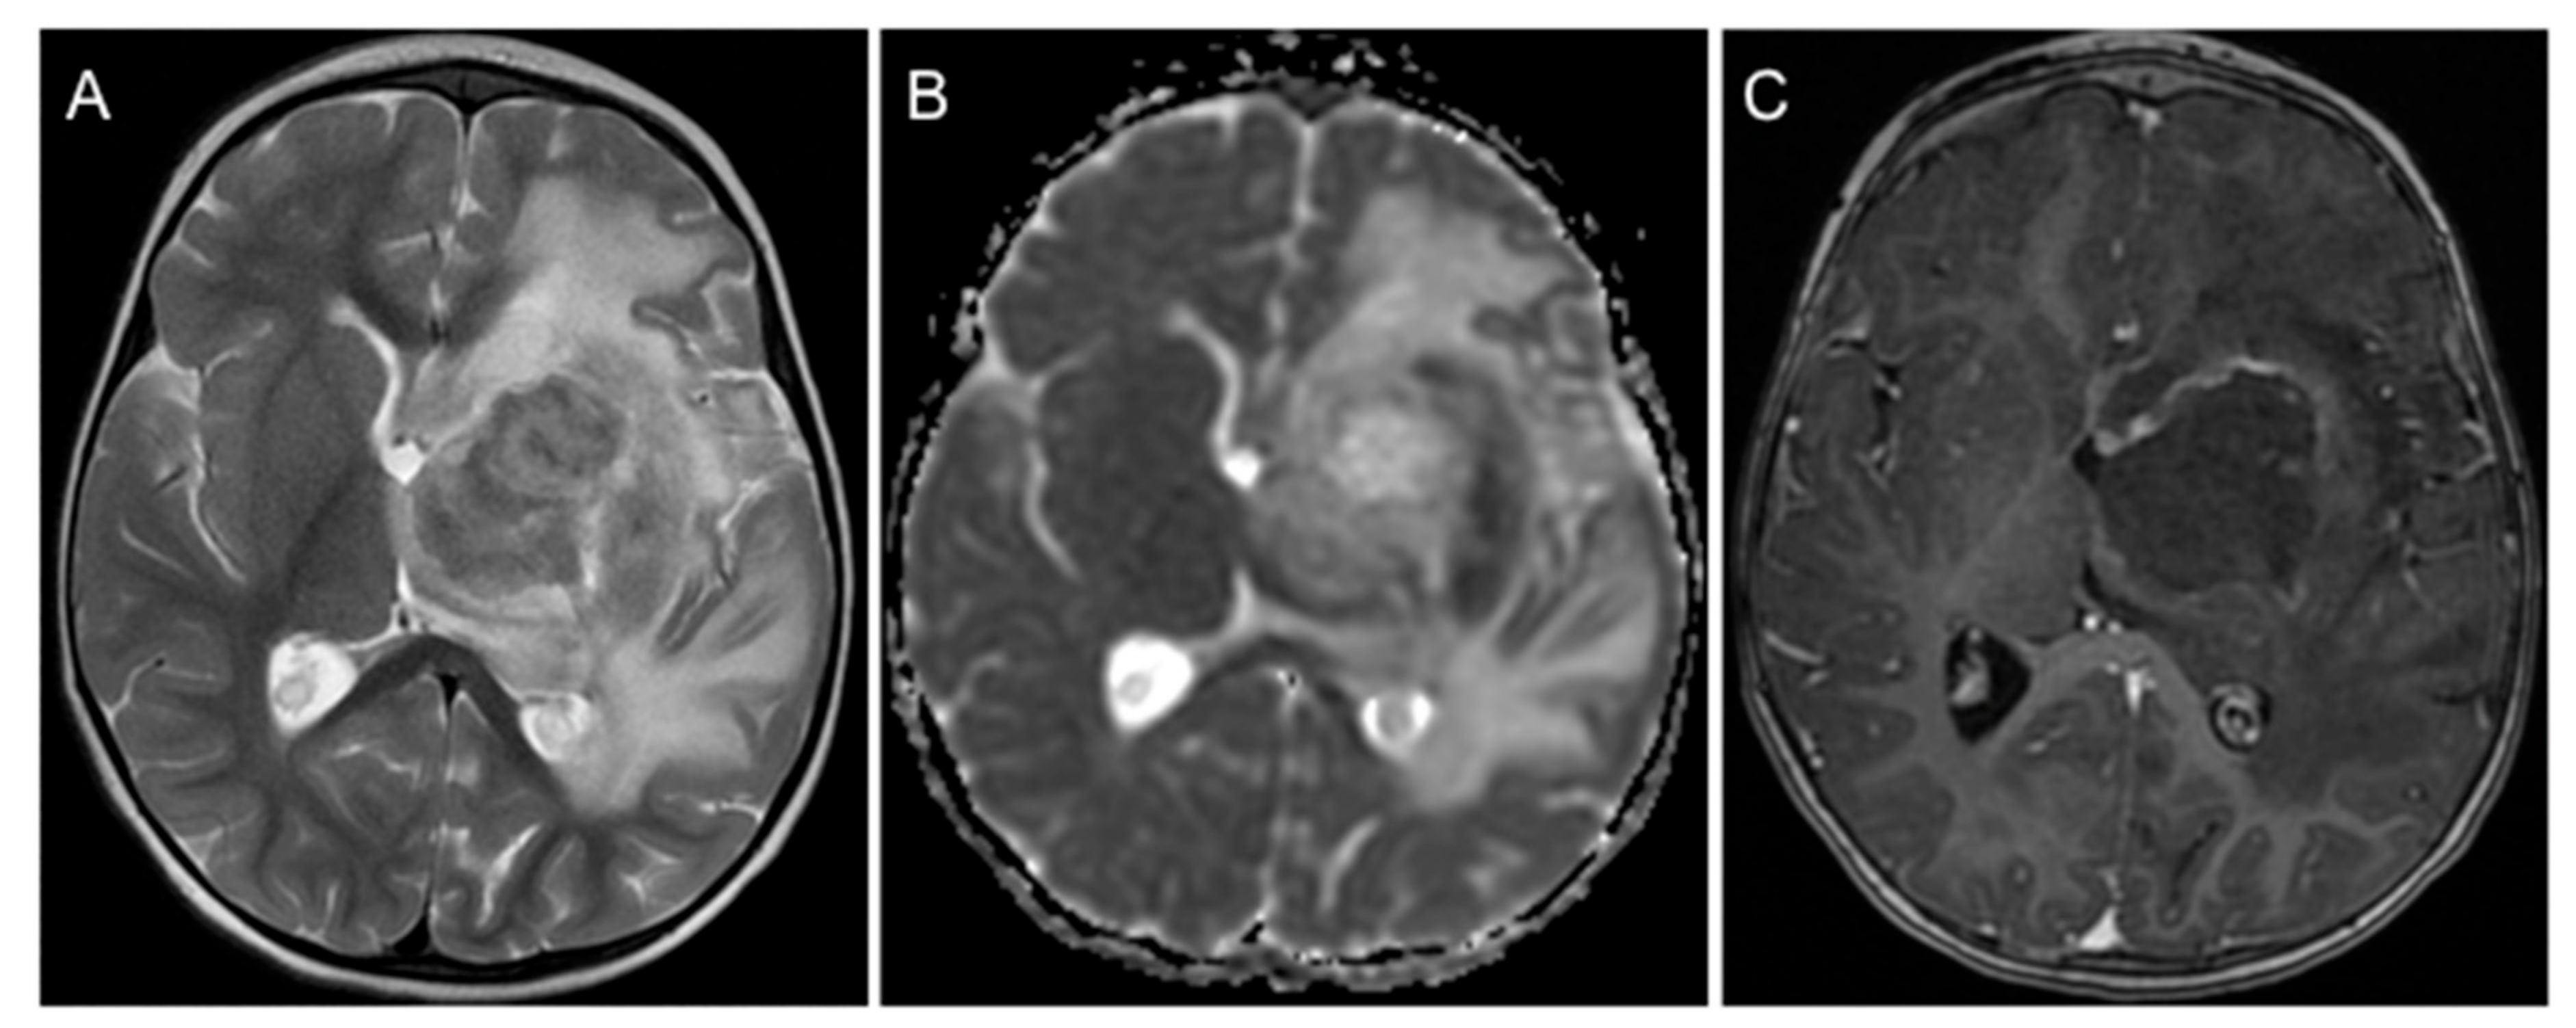

2. Case Presentation